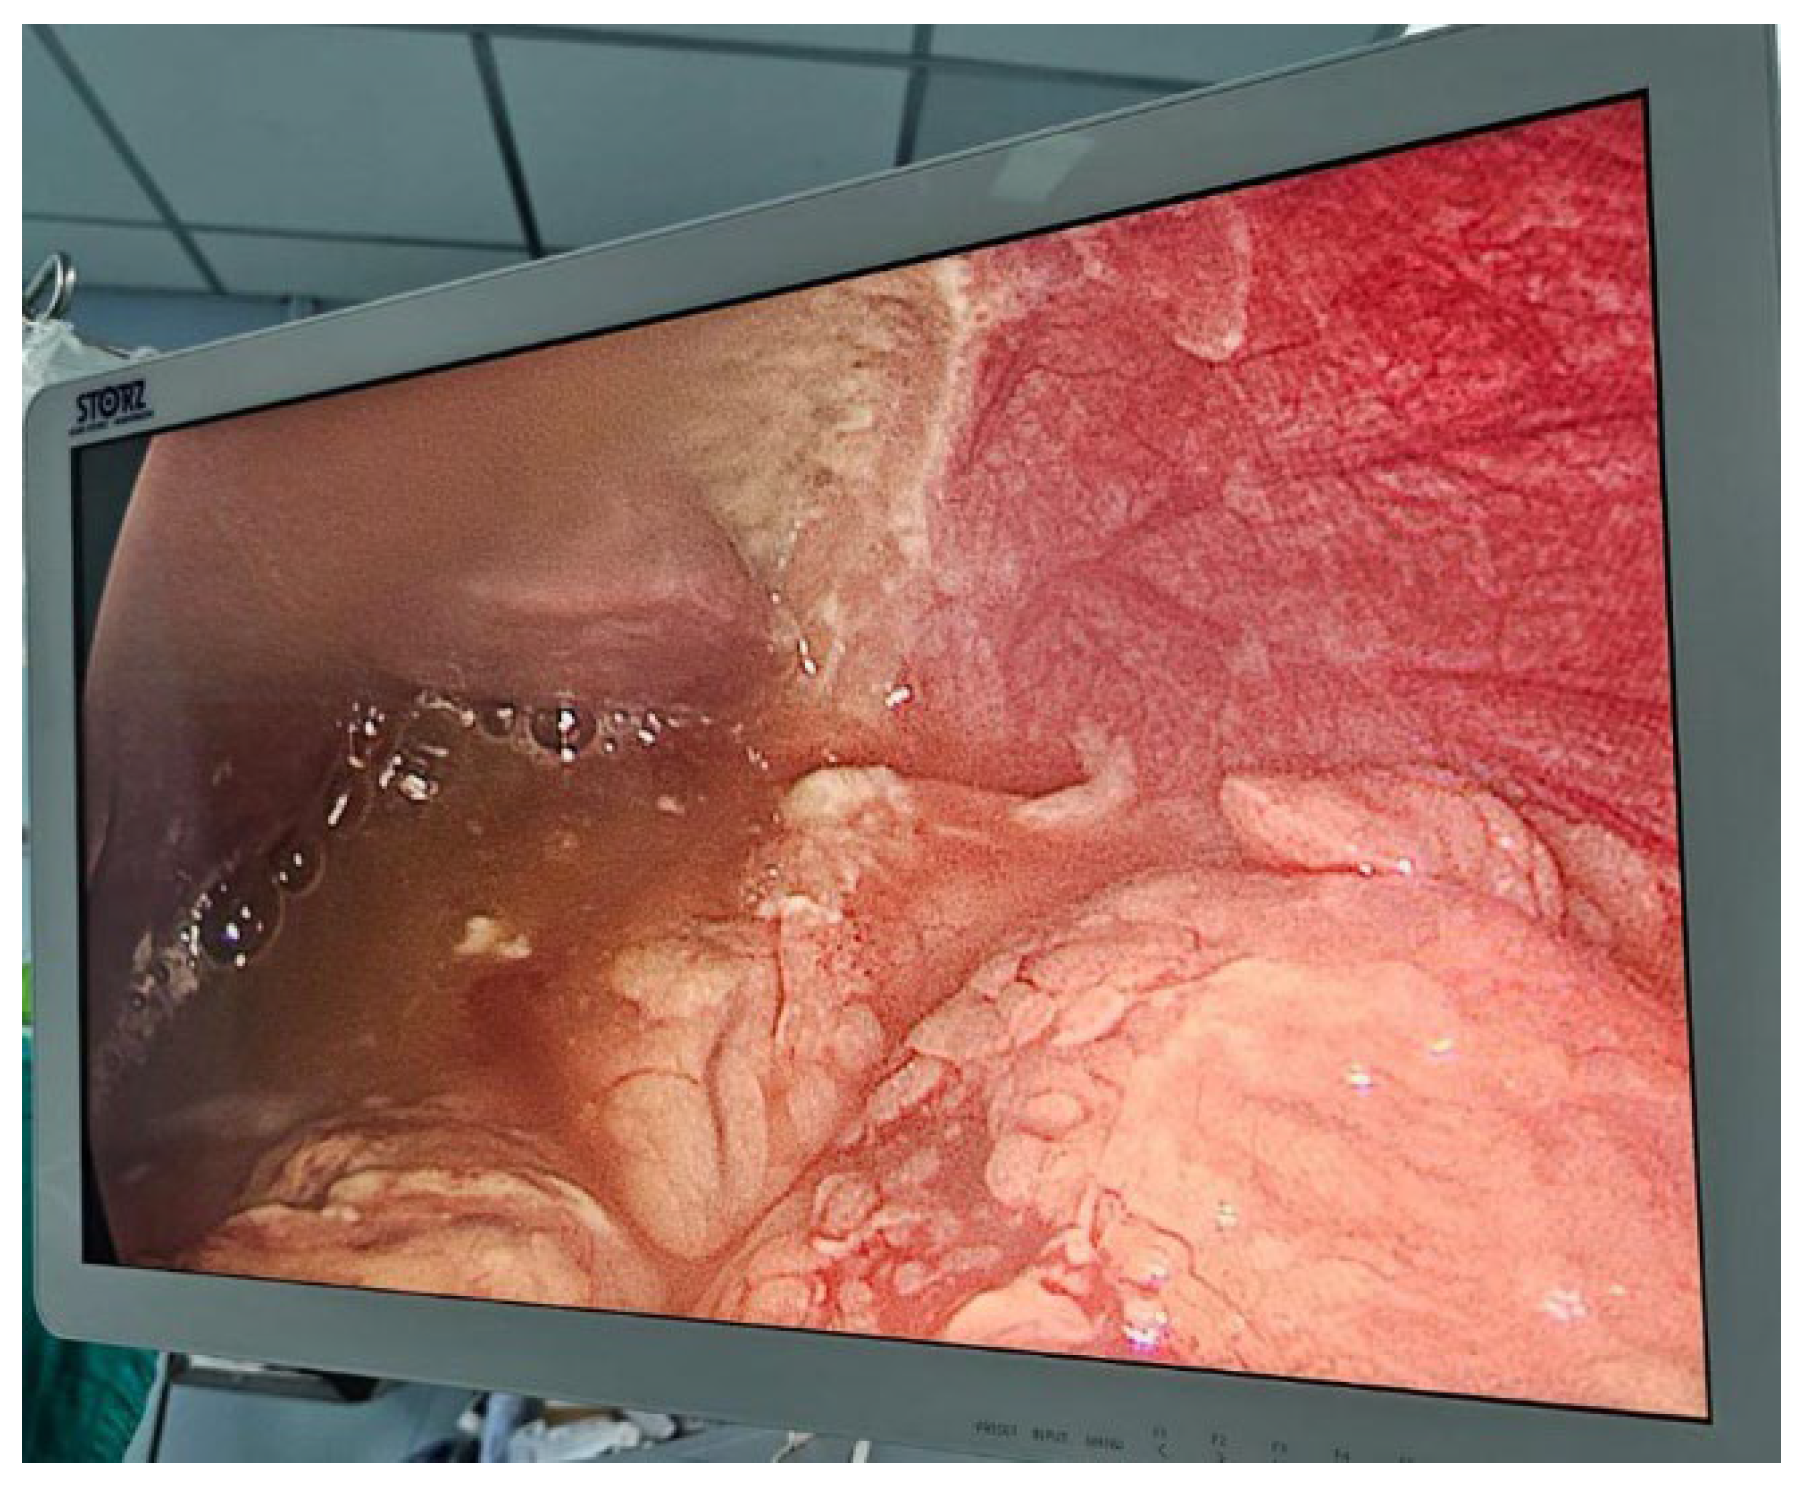

In May 2023, she underwent conversion to laparoscopic gastric bypass, with manual gastro-jejunal anastomosis. one month after she developed new episodes of salivation and poor tolerance to soft and solid diet. Two successful endoscopic dilations were performed [Figure 8], but the symptoms persisted, ranging from daily to 3 times a week. Supplementation of vitamins and protein were indicated. During this period a conventional appendectomy was performed for acute inflammatory abdomen. A new endoscopic dilation was performed, 10 months after surgery, with triamcinolone injection.

Figure 8. Endoscopy shows tortuous gastric pouch with distal stenosis at the site of the gastrojejunostomy. Synthesis material is observed along with inflammatory process.